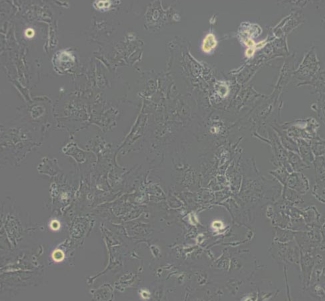

2. 细胞名称:Hs 578T(人乳腺癌细胞)

7. 细胞类型:上皮细胞样

8. 生长特性:贴壁细胞

形态特征:最初为多角形,经传代选择后呈现星形细胞形态;